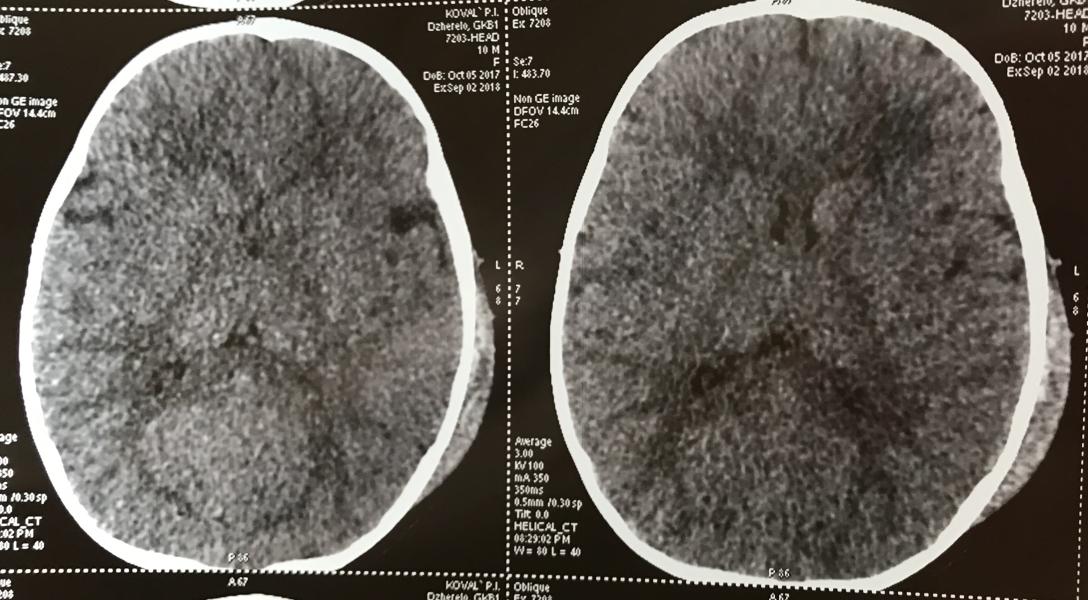

В результате сотрясение, ушиб головного мозга, трещина через 2 кости и гематома огромная!!! Благо, что наружу вытекла, а не в мозг...